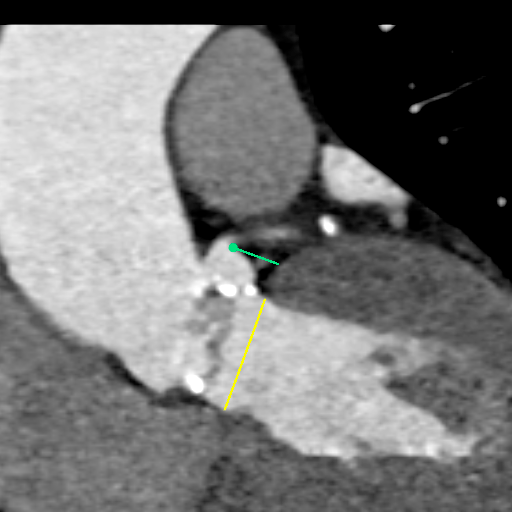

主动脉CT

主动脉瓣环平均直径:22.4mm

左室流出道平均直径:23.2

左冠脉开口:10mm

右冠脉开口高度:14.7mm

患者为功能性二叶瓣,左右瓣叶融合,左冠脉开口低,窦部大,冠脉风险低。

袁义强院长总结了该病例特点:功能性二叶瓣主动脉瓣狭窄,患者有心衰症状,解剖适合TAVR,年龄66岁,存在明确TAVR手术适应症。选择右股动脉入路,根据CT测量分析选择瓣膜大小,窦部情况可,瓣环平均直径22.4mm,选择植入24mm瓣膜。

监护麻醉,经右侧股动脉全麻行TAVR,选用22mm球囊扩张,查看冠脉风险VitaFlow24瓣膜植入。